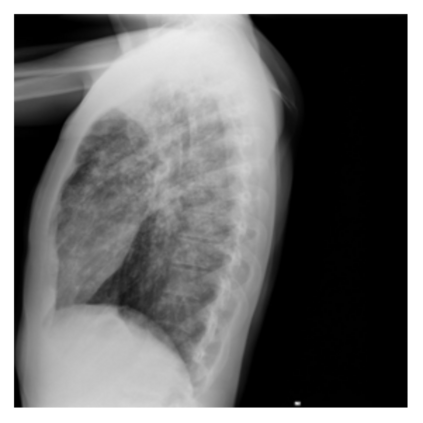

The evaluation of infectious disease processes on radiologic images is an important and challenging task in medical image analysis. Pulmonary infections can often be best imaged and evaluated through computed tomography (CT) scans, which are often not available in low-resource environments and difficult to obtain for critically ill patients. On the other hand, X-ray, a different type of imaging procedure, is inexpensive, often available at the bedside and more widely available, but offers a simpler, two dimensional image. We show that by relying on a model that learns to generate CT images from X-rays synthetically, we can improve the automatic disease classification accuracy and provide clinicians with a different look at the pulmonary disease process. Specifically, we investigate Tuberculosis (TB), a deadly bacterial infectious disease that predominantly affects the lungs, but also other organ systems. We show that relying on synthetically generated CT improves TB identification by 7.50% and distinguishes TB properties up to 12.16% better than the X-ray baseline.